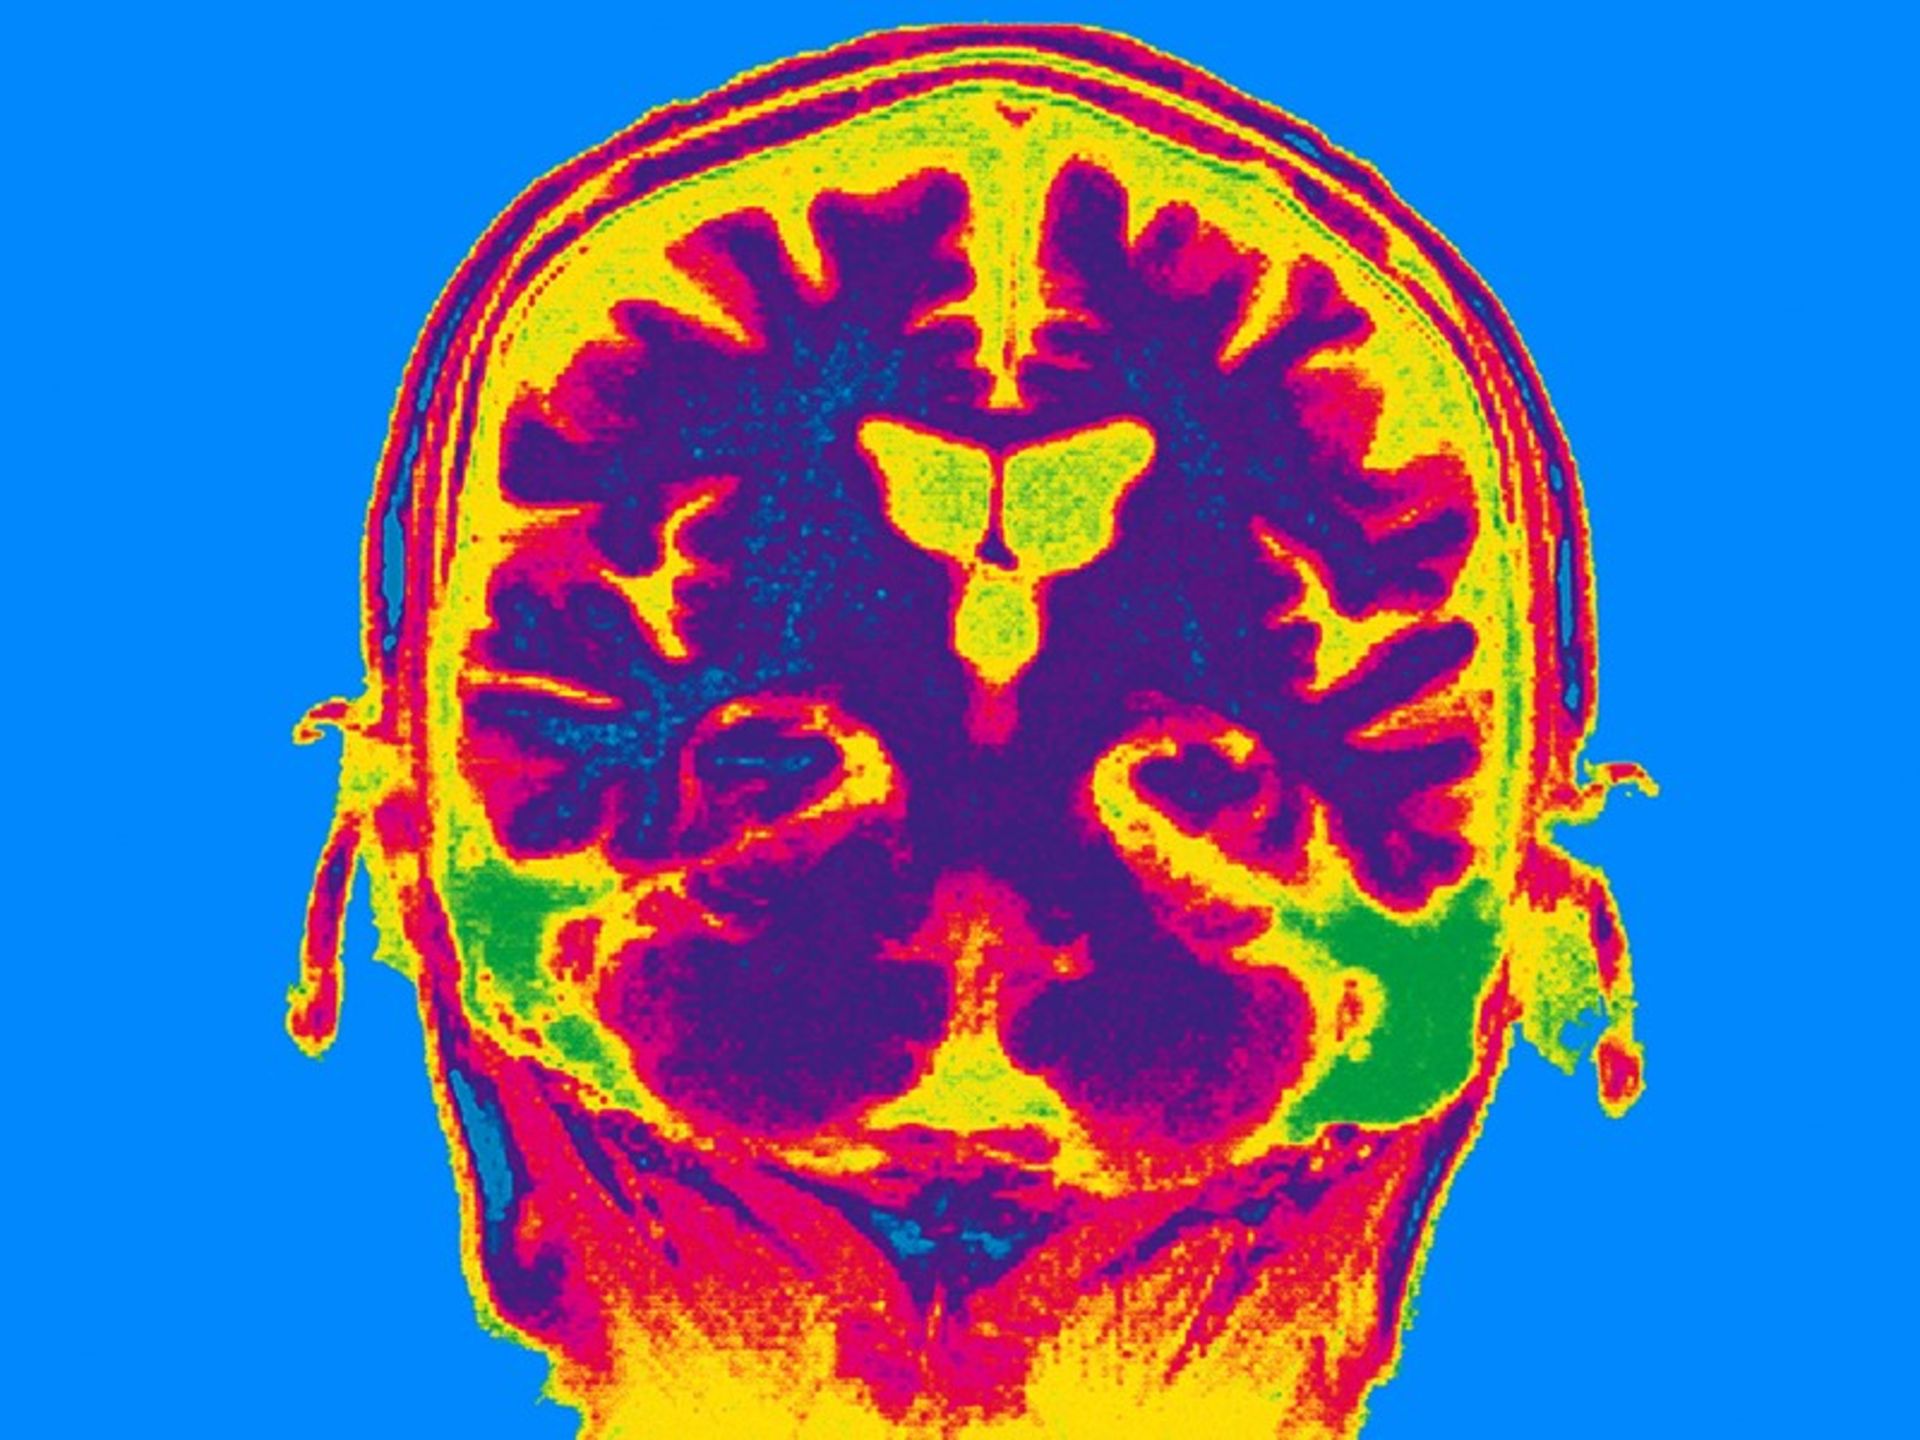

مطالعات قبلی نشان دادهاند که حافظهی بلندمدت و حافظه «مؤثر» یا کاربردی که به مغز امکان ذخیره اطلاعات بهطور موقت را میدهد، توسط مکانیسمها و بخشهایی از مغز کنترل میشوند. تیم پژوهشی با تکیه بر همین تحقیقات نشان دادند که تحریک قشر پیشمغزی پشتی جانبی (ناحیهای نزدیک به جلوی مغز) با جریانهای الکتریکی در فرکانس بالا میتواند حافظه بلندمدت را بهبود بخشد. این در حالی بود که تحریک لوب آهیانه تحتانی (که بیشتر به پشت مغز نزدیک است) با جریانهای الکتریکی با فرکانس پایین، تقویت حافظهی مؤثر یا کاربردی را در پی داشت.

انواع مختلف حافظه توسط بخشهای مختلف مغز کنترل میشود